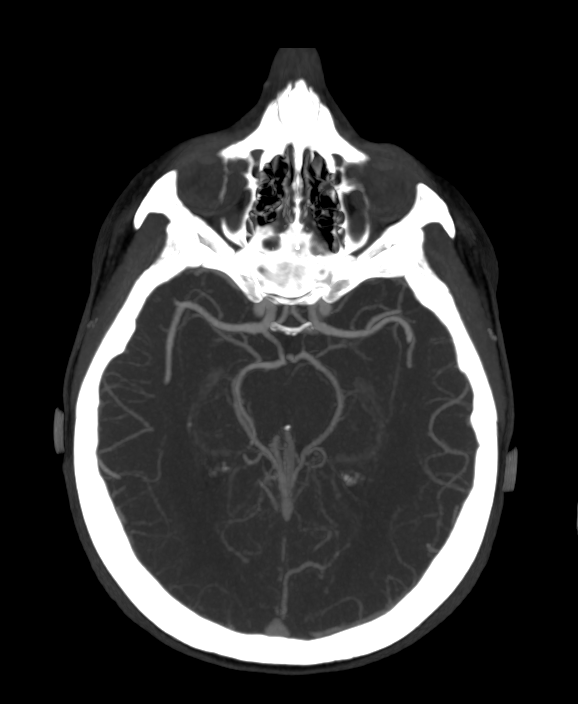

КТ-ангиография сосудов проводится строго по показаниям и имеет ряд особенностей. В первую очередь, учитывается лучевая нагрузка и необходимость введения контрастного вещества, именно поэтому КТ-ангиографию не стоит проводить беременным женщинам и детям до 5 лет (если не имеются жизненные показания).

В клинической практике МР-ангиография является скрининговым методом и только лишь при выявлении каких-либо патологических изменений в сосудах или близлежащих тканях назначают КТ-ангиографию, которая позволяет более детально изучить найденную патологию. УЗ метод является дополнительным и помогает оценить состояние кровотока.